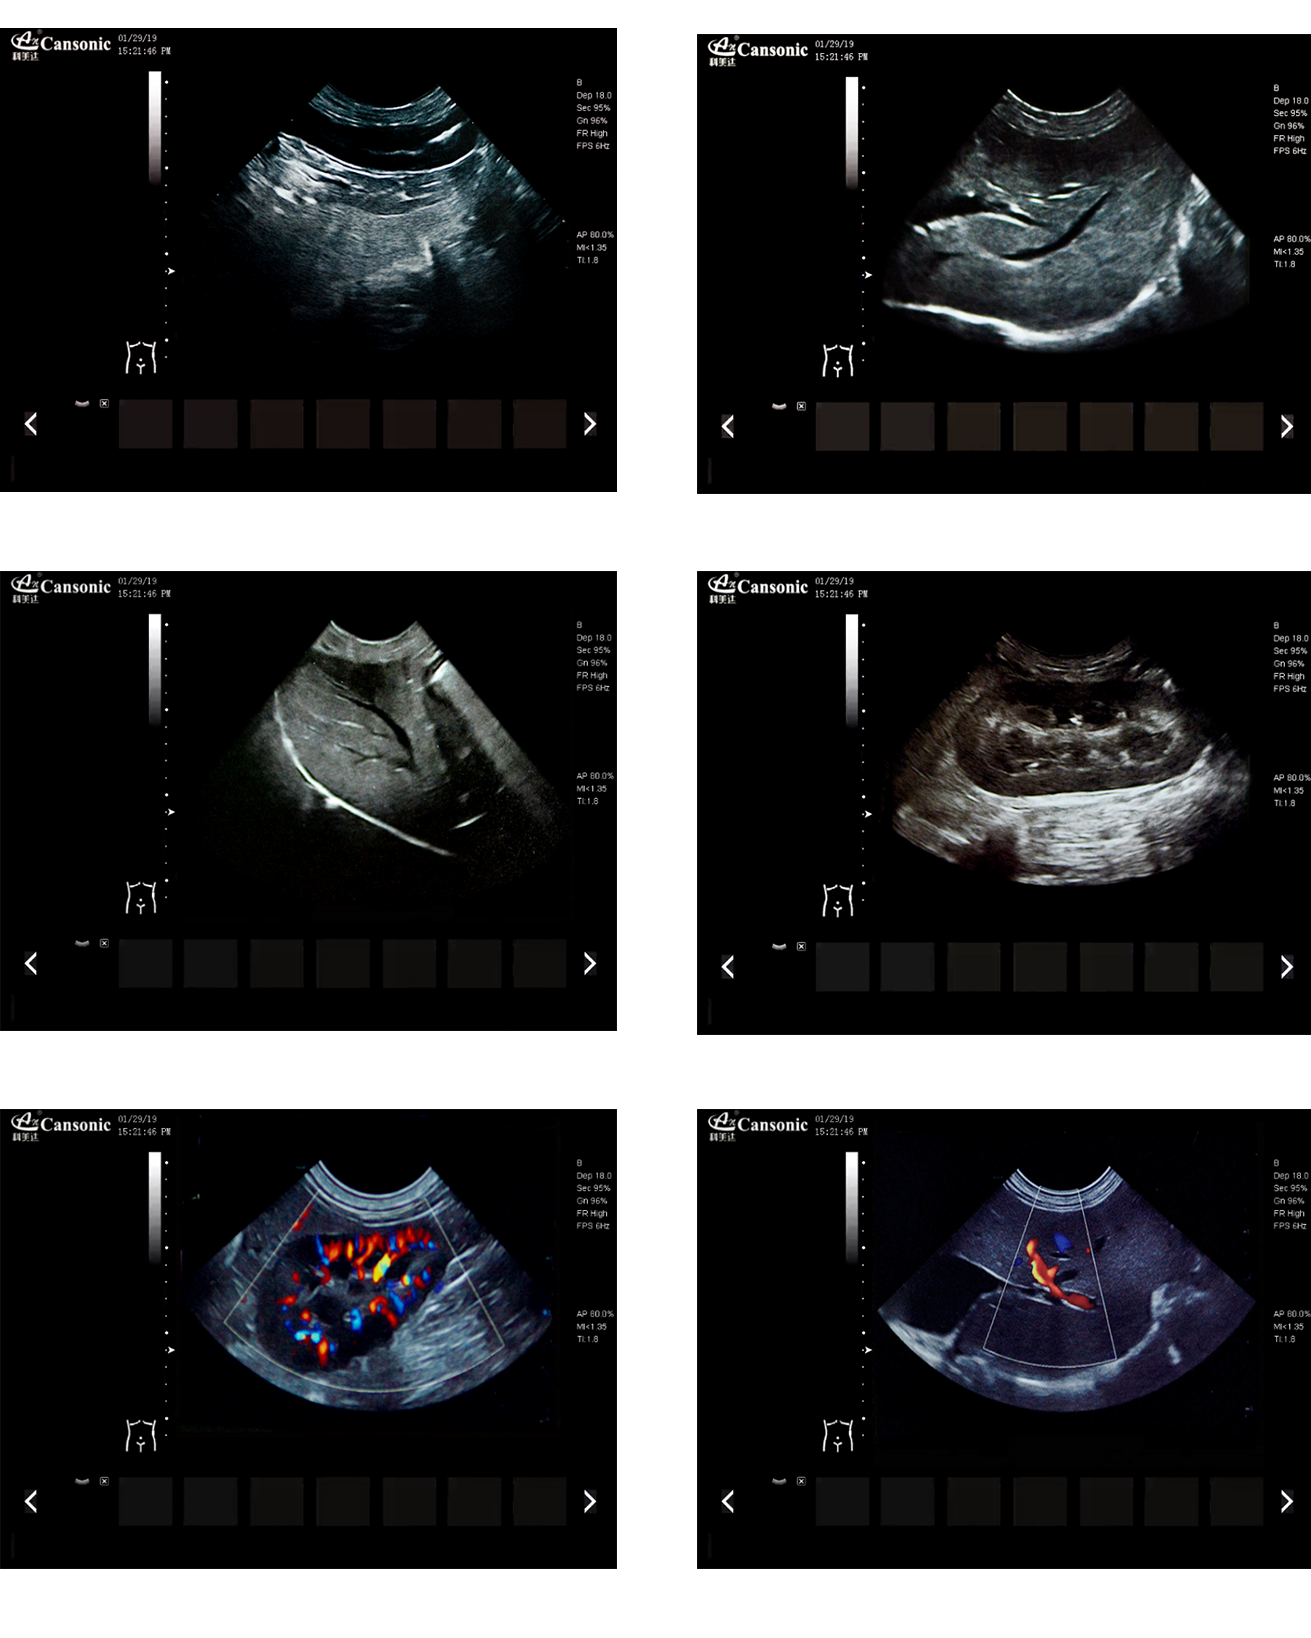

臨床圖示